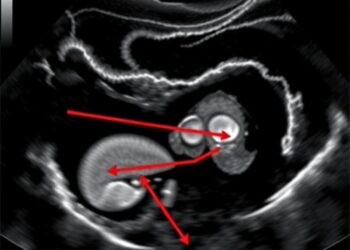

Kiwi Fruit Signals Perinatal Testicular Torsion Risk

Recent advancements in prenatal imaging technology have led to groundbreaking developments in the field of fetal medicine, specifically concerning the ...